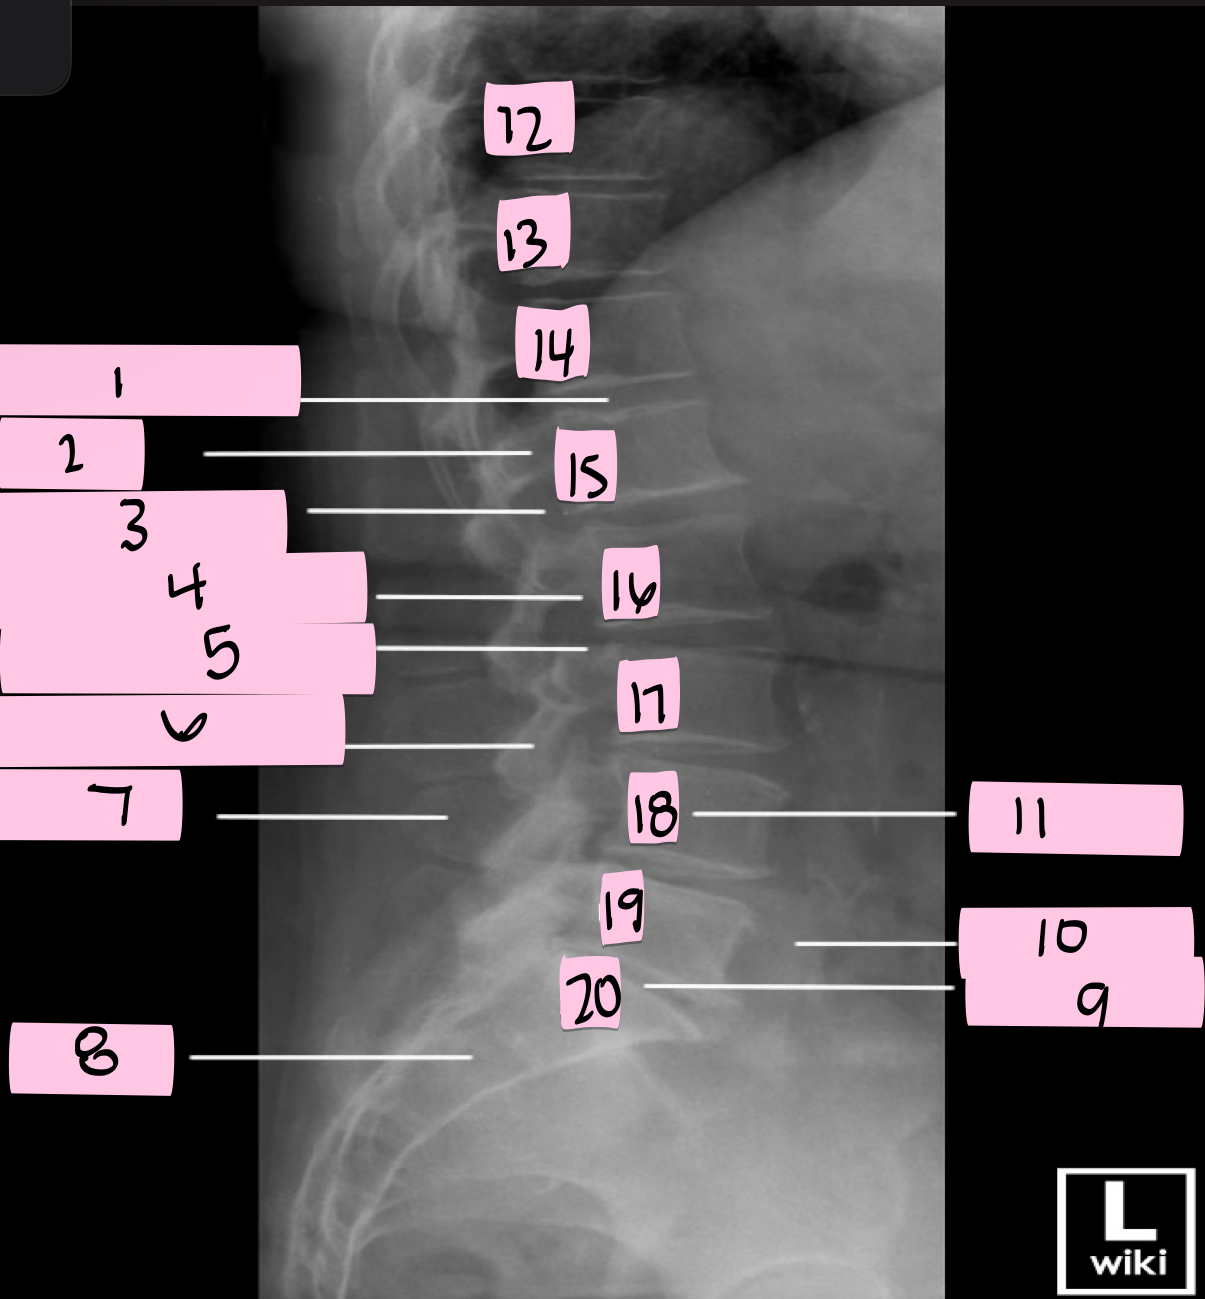

What is 1 pointing to?

Intervertebral disk

What is 2 pointing to?

Pedicle

What is 3 pointing to?

Intervertebral foramen

What is 4 pointing to?

Inferior vertebral notch

What is 5 pointing to?

Superior vertebral notch

What is 6 pointing to?

Inferior articular process

What is 7 pointing to?

Spinous process

What is 8 pointing to?

Sacrum

What is 9 pointing to?

L5 S1 joint

What is 10 pointing to?

Iliac crest

What is 11 pointing to?

Vertebral body (L4)

What is 12 pointing to?

T10

What is 13 pointing to?

T11

What is 14 pointing to?

T12

What is 15 pointing to?

L1

What is 16 pointing to?

L2

What is 17 pointing to?

L3

What is 18 pointing to?

L4

What is 19 pointing to?

L5

What is 20 pointing to?

S1